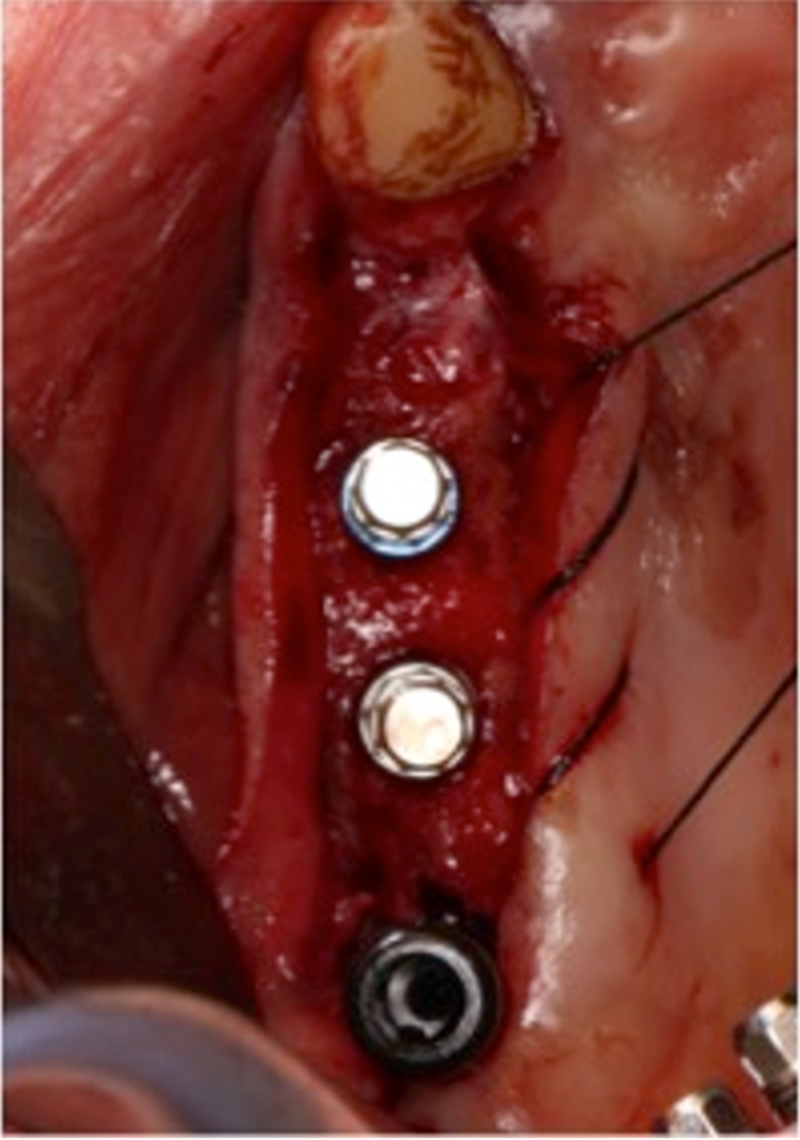

®完成3顆植體的植入,植體位點如術前方案設計,均在同軸線。

®多顆植體位點及角度的精確性,確保后期修復方案順利完成,也使患者能在使用過程中承受最佳的咬合力